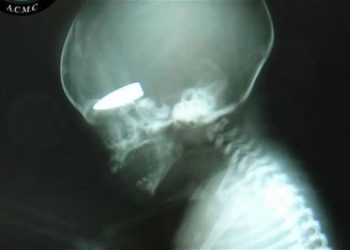

Read moreΟι ελεύθεροι σκοπευτές στη Συρία βάζουν στο στόχαστρό τους παιδιά και τα σημαδεύουν σε σημεία του σώματός τους που μπορεί ...

Read moreΈγκυες γυναίκες είναι στόχοι ελεύθερων σκοπευτών στη Συρία και μάλιστα “επιβραβεύονται” μ΄ αυτό με μερικά πακέτα τσιγάρα.